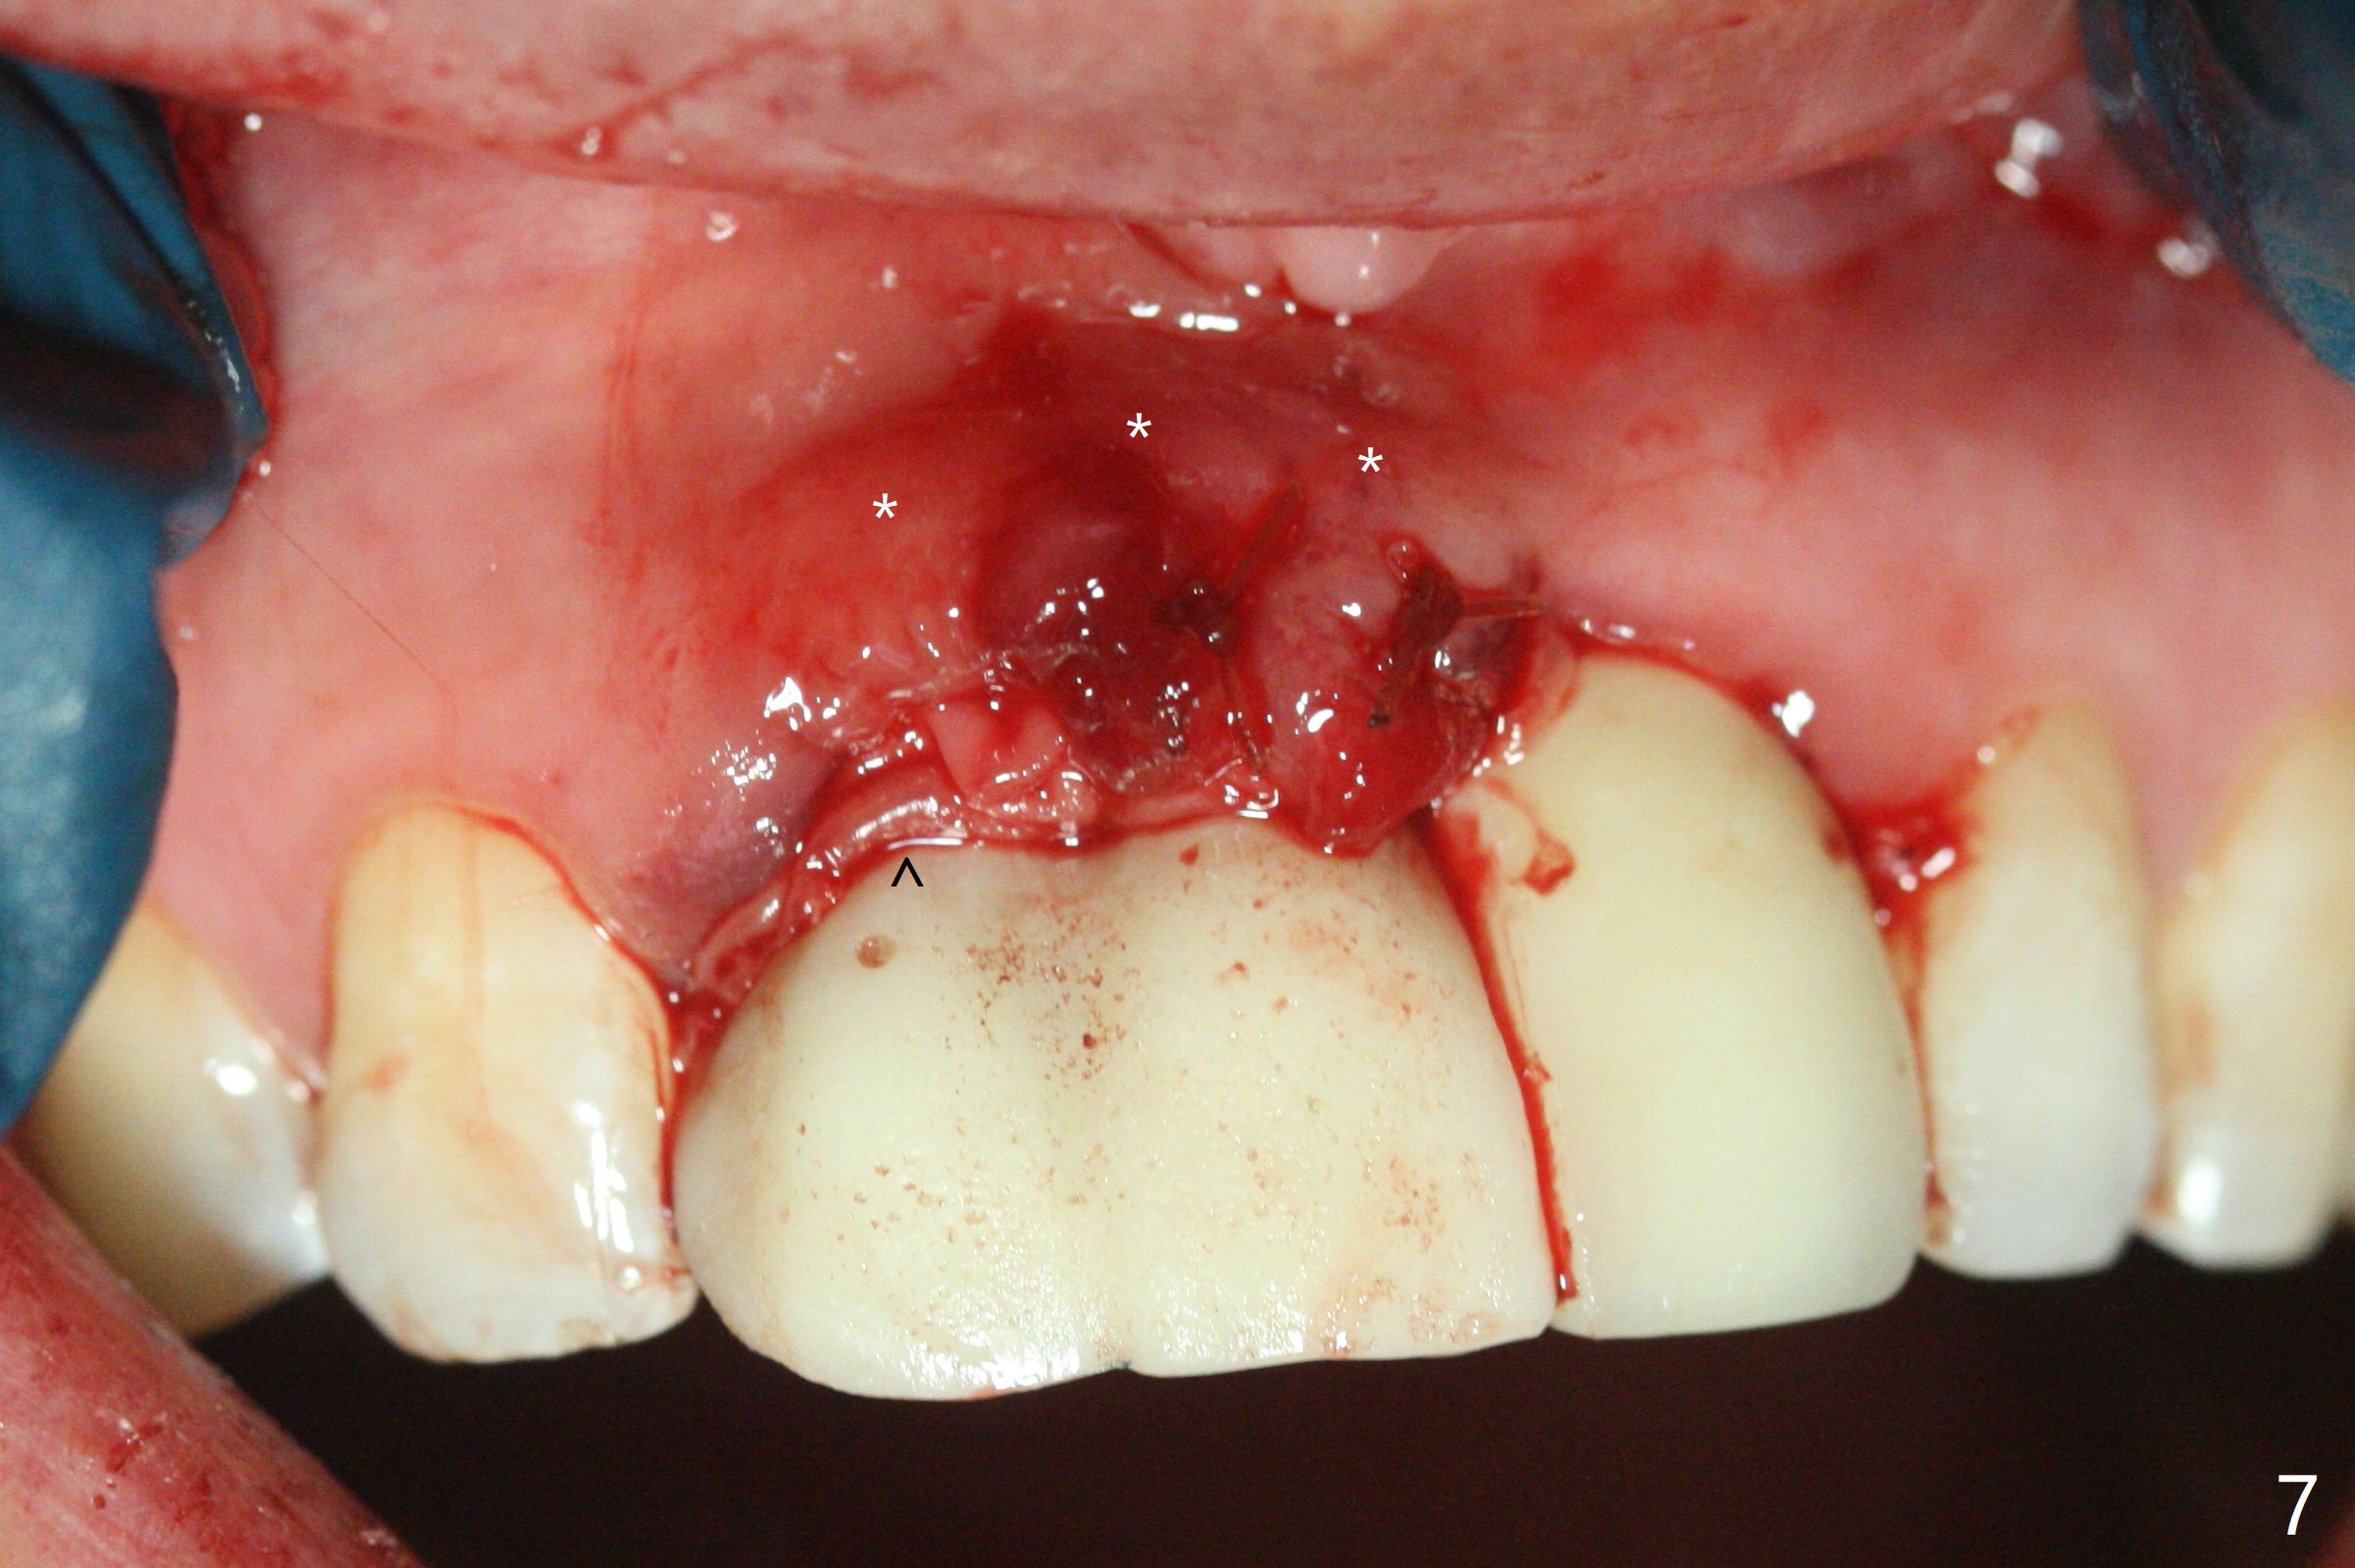

拆除部分桥发现:中,侧切牙牙龈红肿(图一),不利于切口和伤口愈合。不过还是在中切牙区切开,牙龈相当厚,有利于今后牙龈形成凹陷和乳头。坏消息是近远中距离太短,不利于植牙以及今后局部卫生维护,所以决定只在侧切牙种植(图二,三),完成钻洞后,颊侧根尖穿孔植骨,然后植入植体,即刻放置修复基台(图四 (*:牙龈乳头)),暴露基台牙龈缘,制作临时悬臂桥 (图五),两个中切牙牙冠长度差不多,插入临时桥时颊侧牙龈乳头基本形成(图六:*),缝合前颊侧,腭侧牙龈瓣下放置粘性骨块(图七,八:* )和PRF膜(图七:^)。最后使用牙周敷料。但愿术后牙龈炎症消失,形成良好牙龈乳头和pontic concavity。 其实由于口腔卫生习惯,术后十七天颊侧牙龈仍红肿(图九),而腭侧正常。如果口腔卫生改善而红肿依然存在,让实验室制作临时桥。术后一个月颊侧牙龈红肿好些(图十),好像骨粉丢失少许,可能与水枪使用有关。右上1牙冠显得太短(*)。也太肥大,因为右上1切缘太颊侧,与左上1对比(图十一:*)。由于颊侧牙龈(图十二:B)术中推向颊侧,与腭侧(P)牙龈之间放置大量粘性骨粉,术后一个月骨粉(<)形成牙龈,形成凹陷。颊侧萎缩不再明显了。右上1牙冠颈部多加些树脂,牙齿就显得长的多(图十三:箭头)。与侧切牙之间颈部故意留下间隙(*),让牙龈入位(空箭头),形成龈乳头。当右上1临时牙冠切缘(图十四:*)移到腭侧,外形改观不少。下次改善侧切牙唇侧。术后两个月三个星期牙龈红肿好像减轻,牙龈没有进入切牙间隙,干脆用树脂关闭(图十五:> <)。下次减少侧切牙切缘(^),适当增加中切牙长度(上提牙龈)。术后3.5个月植体好像整合,基台完全就位(图十六)。术后3.5个月Pontic凹陷形成,但是1,2之间龈乳头始终无法形成(图十七)。以后类似病例应该多种植一个。此例草率取模,可能需要临时粘固,观察植体近中颊侧所谓瘘道,必要刮治。由于比色不佳,需要实验室颜色更改,病人强化卫生,术后七个月,永久性牙冠粘固前,局部牙龈健康(图十八)。